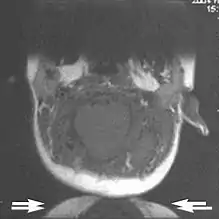

Wrap-around

A wrap-around artifact also known as an aliasing artifact, is a result of mismapping of anatomy that lies outside the field of view but within the slice volume.[4] The selected field of view is smaller than the size of the imaged object. The anatomy is usually displaced to the opposite side of the image (Figs 6 and 7). It can be caused by non-linear gradients or by undersampling of the frequencies contained within the return signal.[1]

The sampling rate must be twice the maximal frequency that occurs in the object (Nyquist sampling limit). If not, the Fourier transform will assign very low values to the frequency signals greater than the Nyquist limit. These frequencies will then ‘wrap around’ to the opposite side of the image, masquerading as low-frequency signals. In the frequency encode direction a filter can be applied to the acquired signal to eliminate frequencies greater than the Nyquist frequency. In the phase encode direction, artifacts can be reduced by an increasing number of phase encode steps (increased image time). For correction, a larger field of view may be chosen.[1]